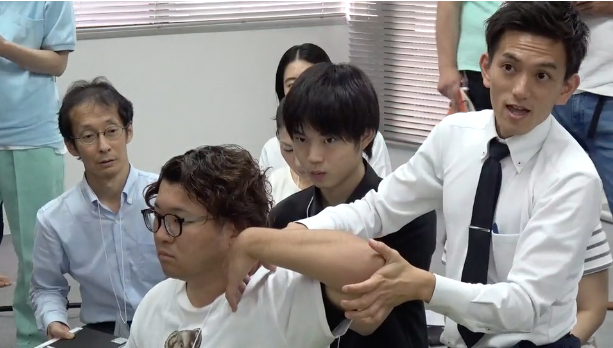

- FCRテクニックは、「押して+動かすだけ」で靭帯・血管・神経を緩めることができるので、場所だけ覚えれば、誰でも簡単にできるテクニックです。

例えば、靭帯に何か原因があるかもしれないと思っても、実際、靭帯にアプローチできる理学療法士は皆無に等しいですし、わかったとしても使いこなせないことがほとんどだと思います。このセッションでは、血管や靭帯などにある原因を素早く見つけ出し、効率良くリリースして、痛みを改善できる3ステップを実例を交えながら詳しくお伝えします。そして、この「3ステップ」は、たとえ臨床1年目の新人だろうが、20年以上の超ベテランだろうが、同じ結果を出すことができます。

なぜ、僕たちがこんなにも疼痛治療の最前線で、結果を出し続けているのか?それは、正確な触診技術にあります。このセッションでは、ほとんどの理学療法士が知らず、学校では決して教えない、僕たちが日々の研究で獲得した、エコー解剖学に基づいた血管・靭帯・神経を確実に触診するための3つのポイントをお伝えします。